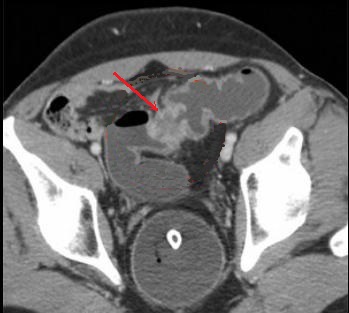

Image radiologique TDM et image de PET/CT des

adenocarcinomae du colon en extension localise et extension

metastasique :